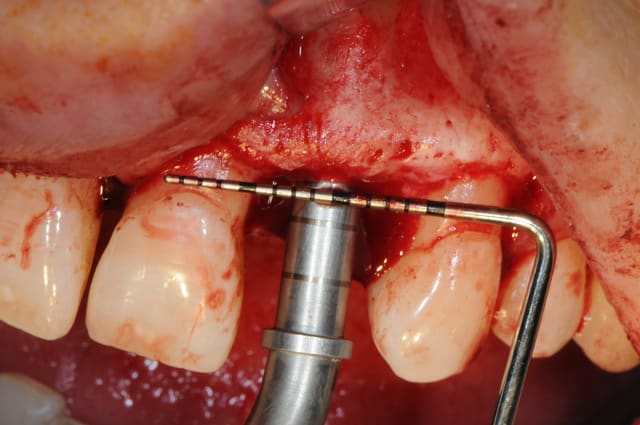

extraction de 12 et 22 pour commencer et pour connaitre la limite maxi d'implantation dans la crête osseuse.

grosse déception quant à la table externe au niveau de 11

pour les axes, j'avoue que je me suis fait avoir comme une bleusaille (mais bon, j'en suis une), je me suis un peu laisser embarquer par l'axe des alvéoles. c'est dure l'implanto.